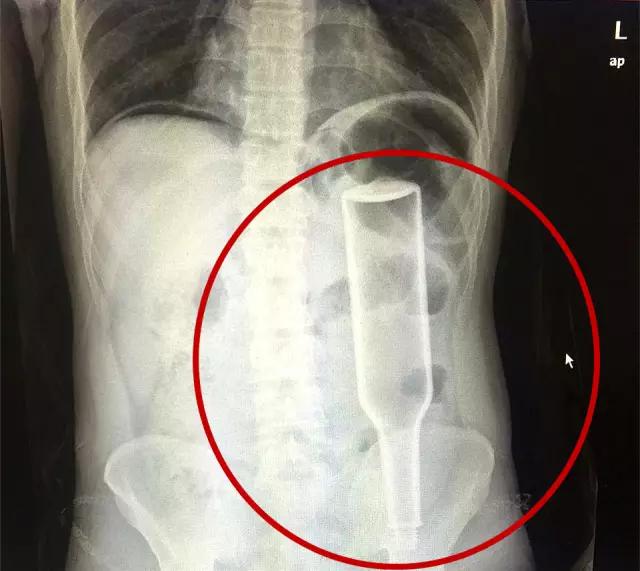

在郑州务工的外地男子王先生(化名),将一个长18厘米、宽5厘米的花露水瓶子从肛门塞到肠道内,因用力过猛,花露水瓶子把直肠戳破,王先生疼痛难忍,来到郑州人民医院就诊,该院普外一病区张春礼大夫成功为其实施手术,目前患者已顺利出院。

“医生,我肚子很痛,快帮我看看。”两周前,王先生捂着肚子来到郑州人民医院求助。对于病情,王先生一开始并没有告诉医生,只是说自己肚子疼得受不了。随后在检查中,张春礼大夫发现,王先生的下腹部内显示有一个完整玻璃瓶的模样。在医生的详细询问下,王先生才不好意思地道出隐情。王先生说自己试着把花露水瓶塞到肛门中,没想到用力过猛,瓶子完全塞进腹腔,肚子越来疼痛难忍,随后,他忍着巨痛来到郑州人民医院。

从检查片来看,瓶子已经塞到了直肠和乙状结肠的交界处,这是一个拐角处,瓶子死死地卡在此处,且显示右侧膈下有游离气体,提示消化道穿孔,结合王先生的情况,张春礼大夫考虑其为左侧大肠穿孔。加之王先生腹部疼痛难忍,张大夫立即联系手术室为其实施急诊手术。原本计划打开患者腹腔后,将把瓶子顺着肠道的方向,从腹腔内推出来。可是,打开腹腔后,令张大夫大吃一惊,瓶子“砰”的一下弹了出来!因王先生用力过猛,造成乙状结肠及直肠交接处破裂。手术第一步将花露水瓶取出;第二步,分离乙状结肠系膜及血管;第三步,切除破裂的直肠乙状结肠交接处肠管;第四步,缝合关闭直肠上段,将近端乙状结肠提出在王先生左下腹部造个瘘,用于患者临时排便。